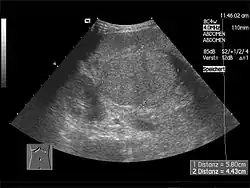

Ultrasonografia (USG)

Ultrasonografia ze względu na niską czułość u pacjentów z marskością wątroby w znacznym stopniu została zastąpiona przez tomografię komputerową i obrazowanie metodą rezonansu magnetycznego. W dużych zmianach ultrasonografia odznacza się wysoką czułością i swoistością, jednak jest mniej wiarygodna dla zmian mniejszych, w których można by zaoferować leczenie radykalne. Dla zmian 3–5 cm czułość wynosi około 80–95%, a w zmianach o wielkości 1 cm już tylko 60–80%[221]. USG z kontrastem (CEUS) w postaci helu i dwutlenku węgla może pozwolić poprawić czułość badania[222][223][224][211]. W optymalnych warunkach badania metoda może wykazywać porównywalną skuteczność w diagnostyce zmian w wątrobie[225]. CEUS może być używany w początkowym etapie diagnostycznym, jednak złotym standardem pozostają TK i MRI[226]. Ultrasonografia dopplerowska ułatwia odróżnienie zmian łagodnych lub przerzutowych od raka wątrobowokomórkowego, w którym typowo są widoczne wzory rozgałęzień naczyń z prędkością przepływu większą niż przy zmianach łagodnych lub przerzutowych. USG doplerowskie pomaga wykryć w żyle wrotnej małe skrzepliny związane z inwazją guza[211][227][228]. Ultrasonografia nadaje się do zastosowania u pacjentów z przeciwwskazaniami do tomografii komputerowej: uczulonych na jodowe środki kontrastowe, z niewydolnością nerek oraz pacjentek w ciąży[229].

USG jest najbardziej odpowiednim badaniem przesiewowym u pacjentów w grupie ryzyka. Charakteryzuje się czułością 60–90% i specyficznością blisko 90%, badanie jest mniej skuteczne w wykrywaniu wczesnych postaci (czułość 63%)[245]. Wykazano przewagę badania przesiewowego przeprowadzanego co 6 miesięcy nad badaniem przeprowadzanym co 12 miesięcy[245]. Jego efektywność jest mocno zależna od umiejętności operatora i jakości urządzenia.